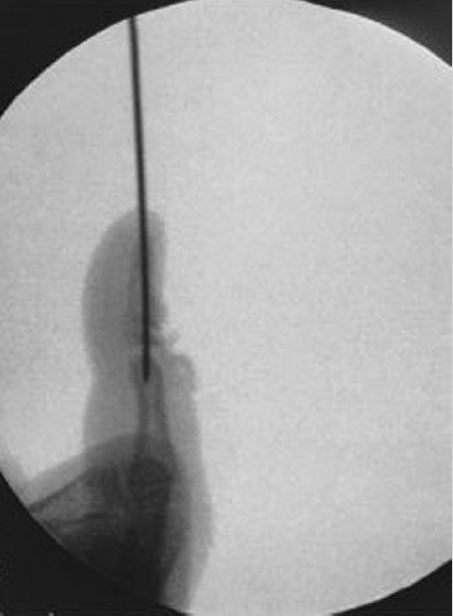

Surgical intervention is reserved for open injuries with associated nailfold/skin lacerations. If the fracture is open and/or the nail plate has been dislodged from the eponchial fold, surgical irrigation and debridement as well as fracture reduction is warranted. Any interposed germinal matrix has to be excised from the physis to limit the degree of nail deformity and minimize the likelihood of bone growth disturbance. The necessity of skeletal fixation is dependent upon the stability of the fracture following reduction but it is not mandatory (► Fig. 31.3 and ► Fig. 31.4).